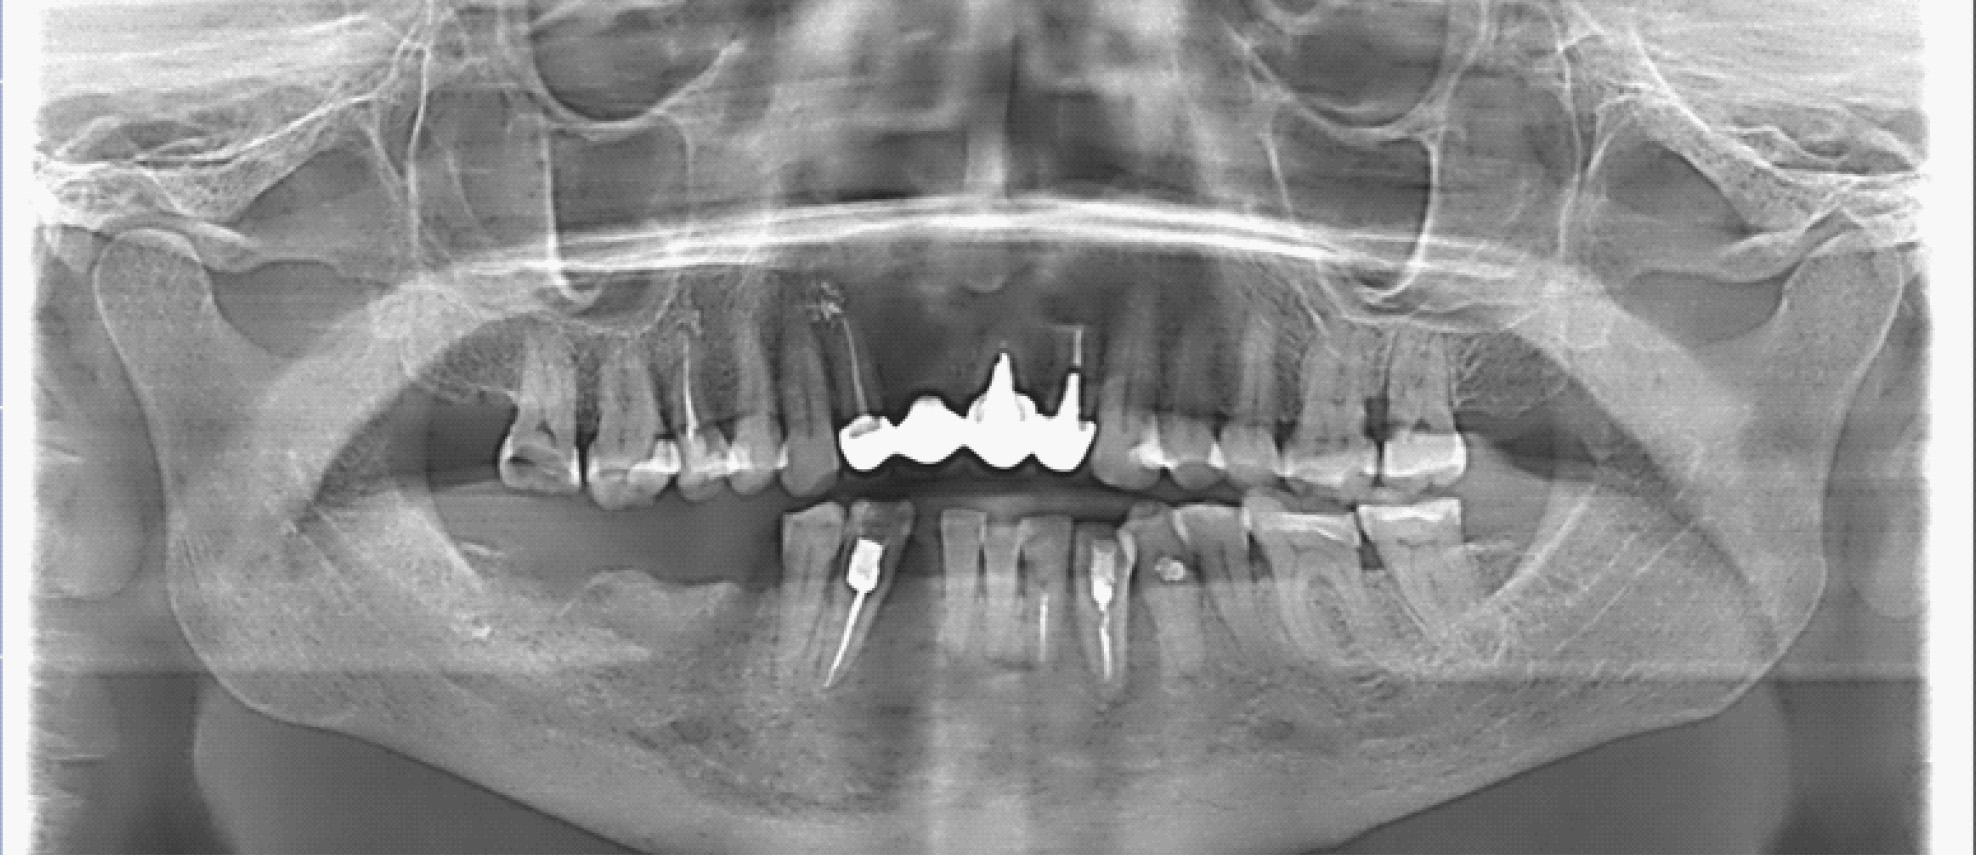

За период лечения пациентки Б. было выполнено хирургическое лечение в следующем объеме: кюретаж лунок удаленных зубов, частичная секвестрэктомия, резекция альвеолярной части нижней челюсти справа, вскрытие и дренирование гнойных очагов в стадии обострения патологического процесса. Отмечалось улучшение клинической и рентгенологической картины в полости рта (рис. 5, 6).

Рис. 5. Клинические проявления бисфосфонатного остеонекроза нижней челюсти справа у пациентки Б. в 2024 году

Рис. 6. Ортопантомограмма на этапе лечения остеонекроза нижней челюсти справа у пациентки Б. в 2024 г.